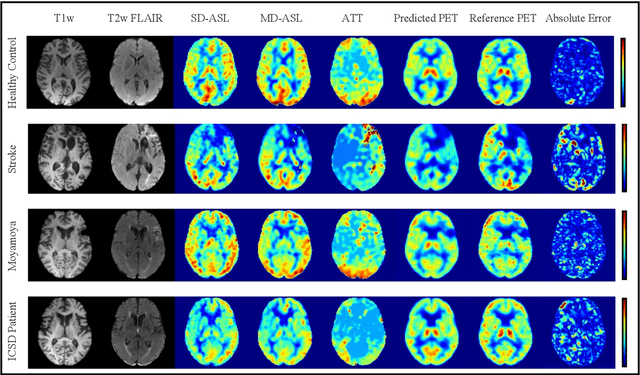

Abstract:Accurate quantification of cerebral blood flow (CBF) is essential for the diagnosis and assessment of a wide range of neurological diseases. Positron emission tomography (PET) with radiolabeled water (15O-water) is considered the gold-standard for the measurement of CBF in humans. PET imaging, however, is not widely available because of its prohibitive costs and use of short-lived radiopharmaceutical tracers that typically require onsite cyclotron production. Magnetic resonance imaging (MRI), in contrast, is more readily accessible and does not involve ionizing radiation. This study presents a convolutional encoder-decoder network with attention mechanisms to predict gold-standard 15O-water PET CBF from multi-sequence MRI scans, thereby eliminating the need for radioactive tracers. Inputs to the prediction model include several commonly used MRI sequences (T1-weighted, T2-FLAIR, and arterial spin labeling). The model was trained and validated using 5-fold cross-validation in a group of 126 subjects consisting of healthy controls and cerebrovascular disease patients, all of whom underwent simultaneous $15O-water PET/MRI. The results show that such a model can successfully synthesize high-quality PET CBF measurements (with an average SSIM of 0.924 and PSNR of 38.8 dB) and is more accurate compared to concurrent and previous PET synthesis methods. We also demonstrate the clinical significance of the proposed algorithm by evaluating the agreement for identifying the vascular territories with abnormally low CBF. Such methods may enable more widespread and accurate CBF evaluation in larger cohorts who cannot undergo PET imaging due to radiation concerns, lack of access, or logistic challenges.

Abstract:Accurate quantification of cerebral blood flow (CBF) is essential for the diagnosis and assessment of cerebrovascular diseases such as Moyamoya, carotid stenosis, aneurysms, and stroke. Positron emission tomography (PET) is currently regarded as the gold standard for the measurement of CBF in the human brain. PET imaging, however, is not widely available because of its prohibitive costs, use of ionizing radiation, and logistical challenges, which require a co-localized cyclotron to deliver the 2 min half-life Oxygen-15 radioisotope. Magnetic resonance imaging (MRI), in contrast, is more readily available and does not involve ionizing radiation. In this study, we propose a multi-task learning framework for brain MRI-to-PET translation and disease diagnosis. The proposed framework comprises two prime networks: (1) an attention-based 3D encoder-decoder convolutional neural network (CNN) that synthesizes high-quality PET CBF maps from multi-contrast MRI images, and (2) a multi-scale 3D CNN that identifies the brain disease corresponding to the input MRI images. Our multi-task framework yields promising results on the task of MRI-to-PET translation, achieving an average structural similarity index (SSIM) of 0.94 and peak signal-to-noise ratio (PSNR) of 38dB on a cohort of 120 subjects. In addition, we show that integrating multiple MRI modalities can improve the clinical diagnosis of brain diseases.